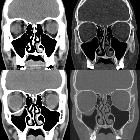

CT

CT is the modality of choice for assessment of the facial skeleton. A full assessment does not require the administration of contrast. Ideally, the acquisition should be performed using the thinnest detector settings, enabling thin-slice reconstructions along three orthogonal planes with a bone algorithm. Additional soft tissue algorithm reconstructions using larger slice thickness and 3D volumetric reconstruction are useful for assessing associated soft tissue injury and gauging facial asymmetry, respectively.

Several imaging features are associated with late enophthalmos :

- surface area of fracture ≥2 cm

- ≥25-50% involvement of inferior or medial orbital walls

- collapse of internal orbital buttress or convex junctional bulge

- internal orbital buttress located at the union between medial and inferior orbital walls

- convex junctional bulge is the posterior continuation of the internal orbital buttress, supporting the orbital contents from posterior

- intraorbital soft tissue herniation volume ≥1.5 cm

- a linear relationship between the volume of intraorbital contents and depth of enophthalmos